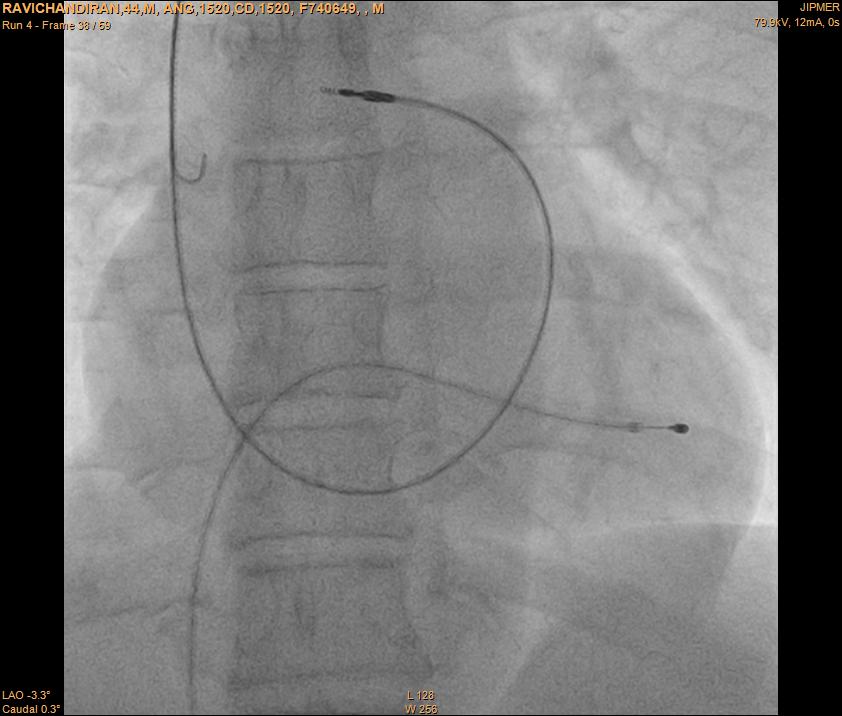

Extra loop

alpha_loop.jpg

Atrial lead placement

Atrial appendage

• Pre-formed J

• J shaped stylet

• Recognize appendage position